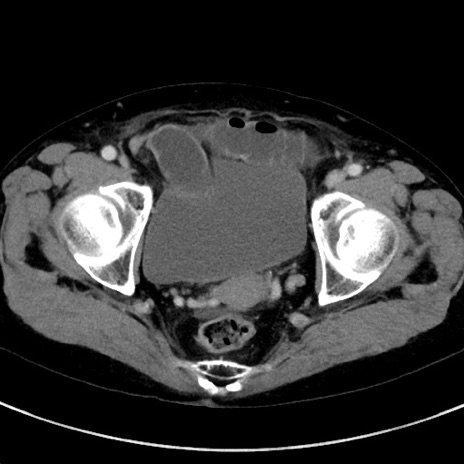

冠状断像

【症例】70歳代女性

【主訴】下腹部痛・嘔吐

【現病歴】2日前より腹痛あり。昨日嘔吐あり。症状改善しないため来院。

【既往歴】胃GISTに対して胃部分切除後。

【身体所見】BT 37.1℃、BP 128/77mmHg、腹部:平坦・軟、下腹部に圧痛あり。

【データ】WBC 10200、CRP 0.31